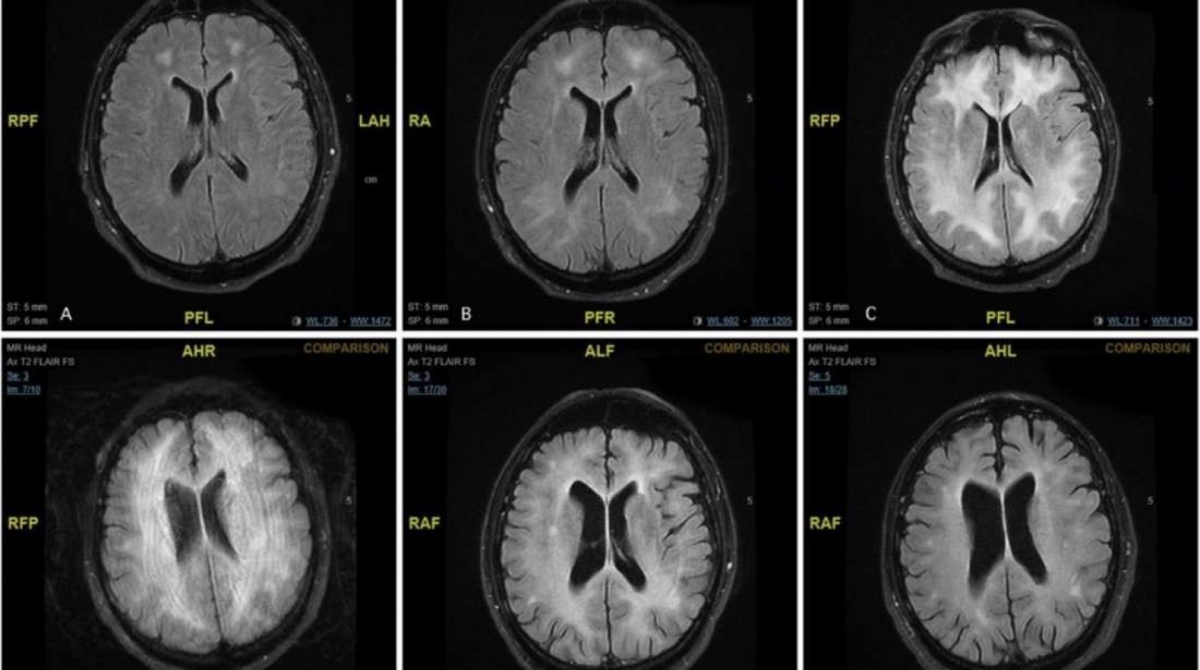

Então ele piorou e se tornou incomunicativo e catatônico. Ele foi submetido a diversos exames, e todos pareciam normais. Menos um: a ressonância magnética, que revelou uma perda de “substância branca”, parte do cérebro que dá suporte e nutrição aos neurônios.

A condição foi diagnosticada como leucoencefalopatia, caracterizada por danos à substância branca, que pode ser causada, que pode ser causada por um infecção viral e bacteriana. Porém, o paciente não tinha nenhum outro sinal de infecção.

Com frequência esses casos de leucoencefalopatia relacionados a cocaína são fatais. Mas o paciente do caso reportado pelo BMJ se recuperou em um ano, e teve resultados normais em testes neurológicos. Mas outras ressonâncias mostraram que ainda havia mudanças na substância branca. Os médicos ministraram remédios para conter a inflamação e melhorar o funcionamento do sistema imune. E o paciente foi para uma clínica de reabilitação para se livrar do vício.